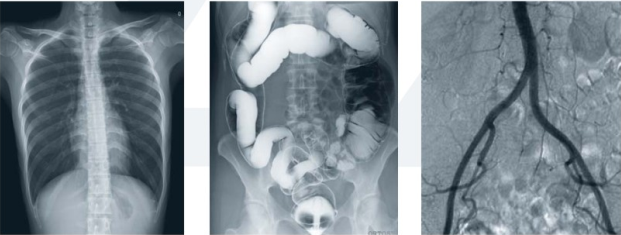

去醫(yī)院看病,經(jīng)常遇到這樣的困惑:DR、CT、MRI這些長(zhǎng)相差不多的醫(yī)學(xué)影像設(shè)備有什么區(qū)別嗎?為什么有的時(shí)候用CT,有的時(shí)候用MRI,甚至有的時(shí)候做了DR還需做CT、MRI,是亂開檢查嗎?還是病情加重了?其實(shí),它們的工作原理不同,各有分工,優(yōu)勢(shì)各異。以下小編帶你一一解讀。

DR(Digital Radiography)是數(shù)字化的拍片機(jī)器。采用非晶硅平板探測(cè)器把穿透人體的X線信息轉(zhuǎn)化為數(shù)字信號(hào),通過計(jì)算機(jī)重新構(gòu)建成圖像并進(jìn)行一系列的處理。DR系統(tǒng)也是各大醫(yī)院的必備“武器”之一。常用于人體胸部及骨骼攝片,也可拍攝其他部位比如腹部、牙齒、頭顱等。

3.對(duì)骨結(jié)構(gòu)、關(guān)節(jié)軟骨及軟組織的顯示優(yōu)于傳統(tǒng)的X線成像,還可進(jìn)行礦物鹽含量的定量分析;易于顯示縱隔結(jié)構(gòu)如血管和氣管;對(duì)結(jié)節(jié)性病變的檢出率高于傳統(tǒng)的X線成像;在觀察腸管積氣、氣腹和結(jié)石等含鈣病變優(yōu)于傳統(tǒng)X線圖像;體層成像優(yōu)于X線體層攝影;胃腸雙對(duì)比造影在顯示胃小區(qū)、微小病變和腸粘膜皺襞上,數(shù)字化圖像優(yōu)于傳統(tǒng)的X線造影。

CT:

CT(Computed Tomography)即電子計(jì)算機(jī)體層掃描。用X射線束對(duì)人體某部一定厚度的層面進(jìn)行掃描,由探測(cè)器接收透過該層面的X射線,轉(zhuǎn)變?yōu)榭梢姽夂螅晒怆娹D(zhuǎn)換變?yōu)殡娦盘?hào),再經(jīng)模擬/數(shù)字轉(zhuǎn)換器(analog/digital converter)轉(zhuǎn)為數(shù)字,輸入計(jì)算機(jī)處理。